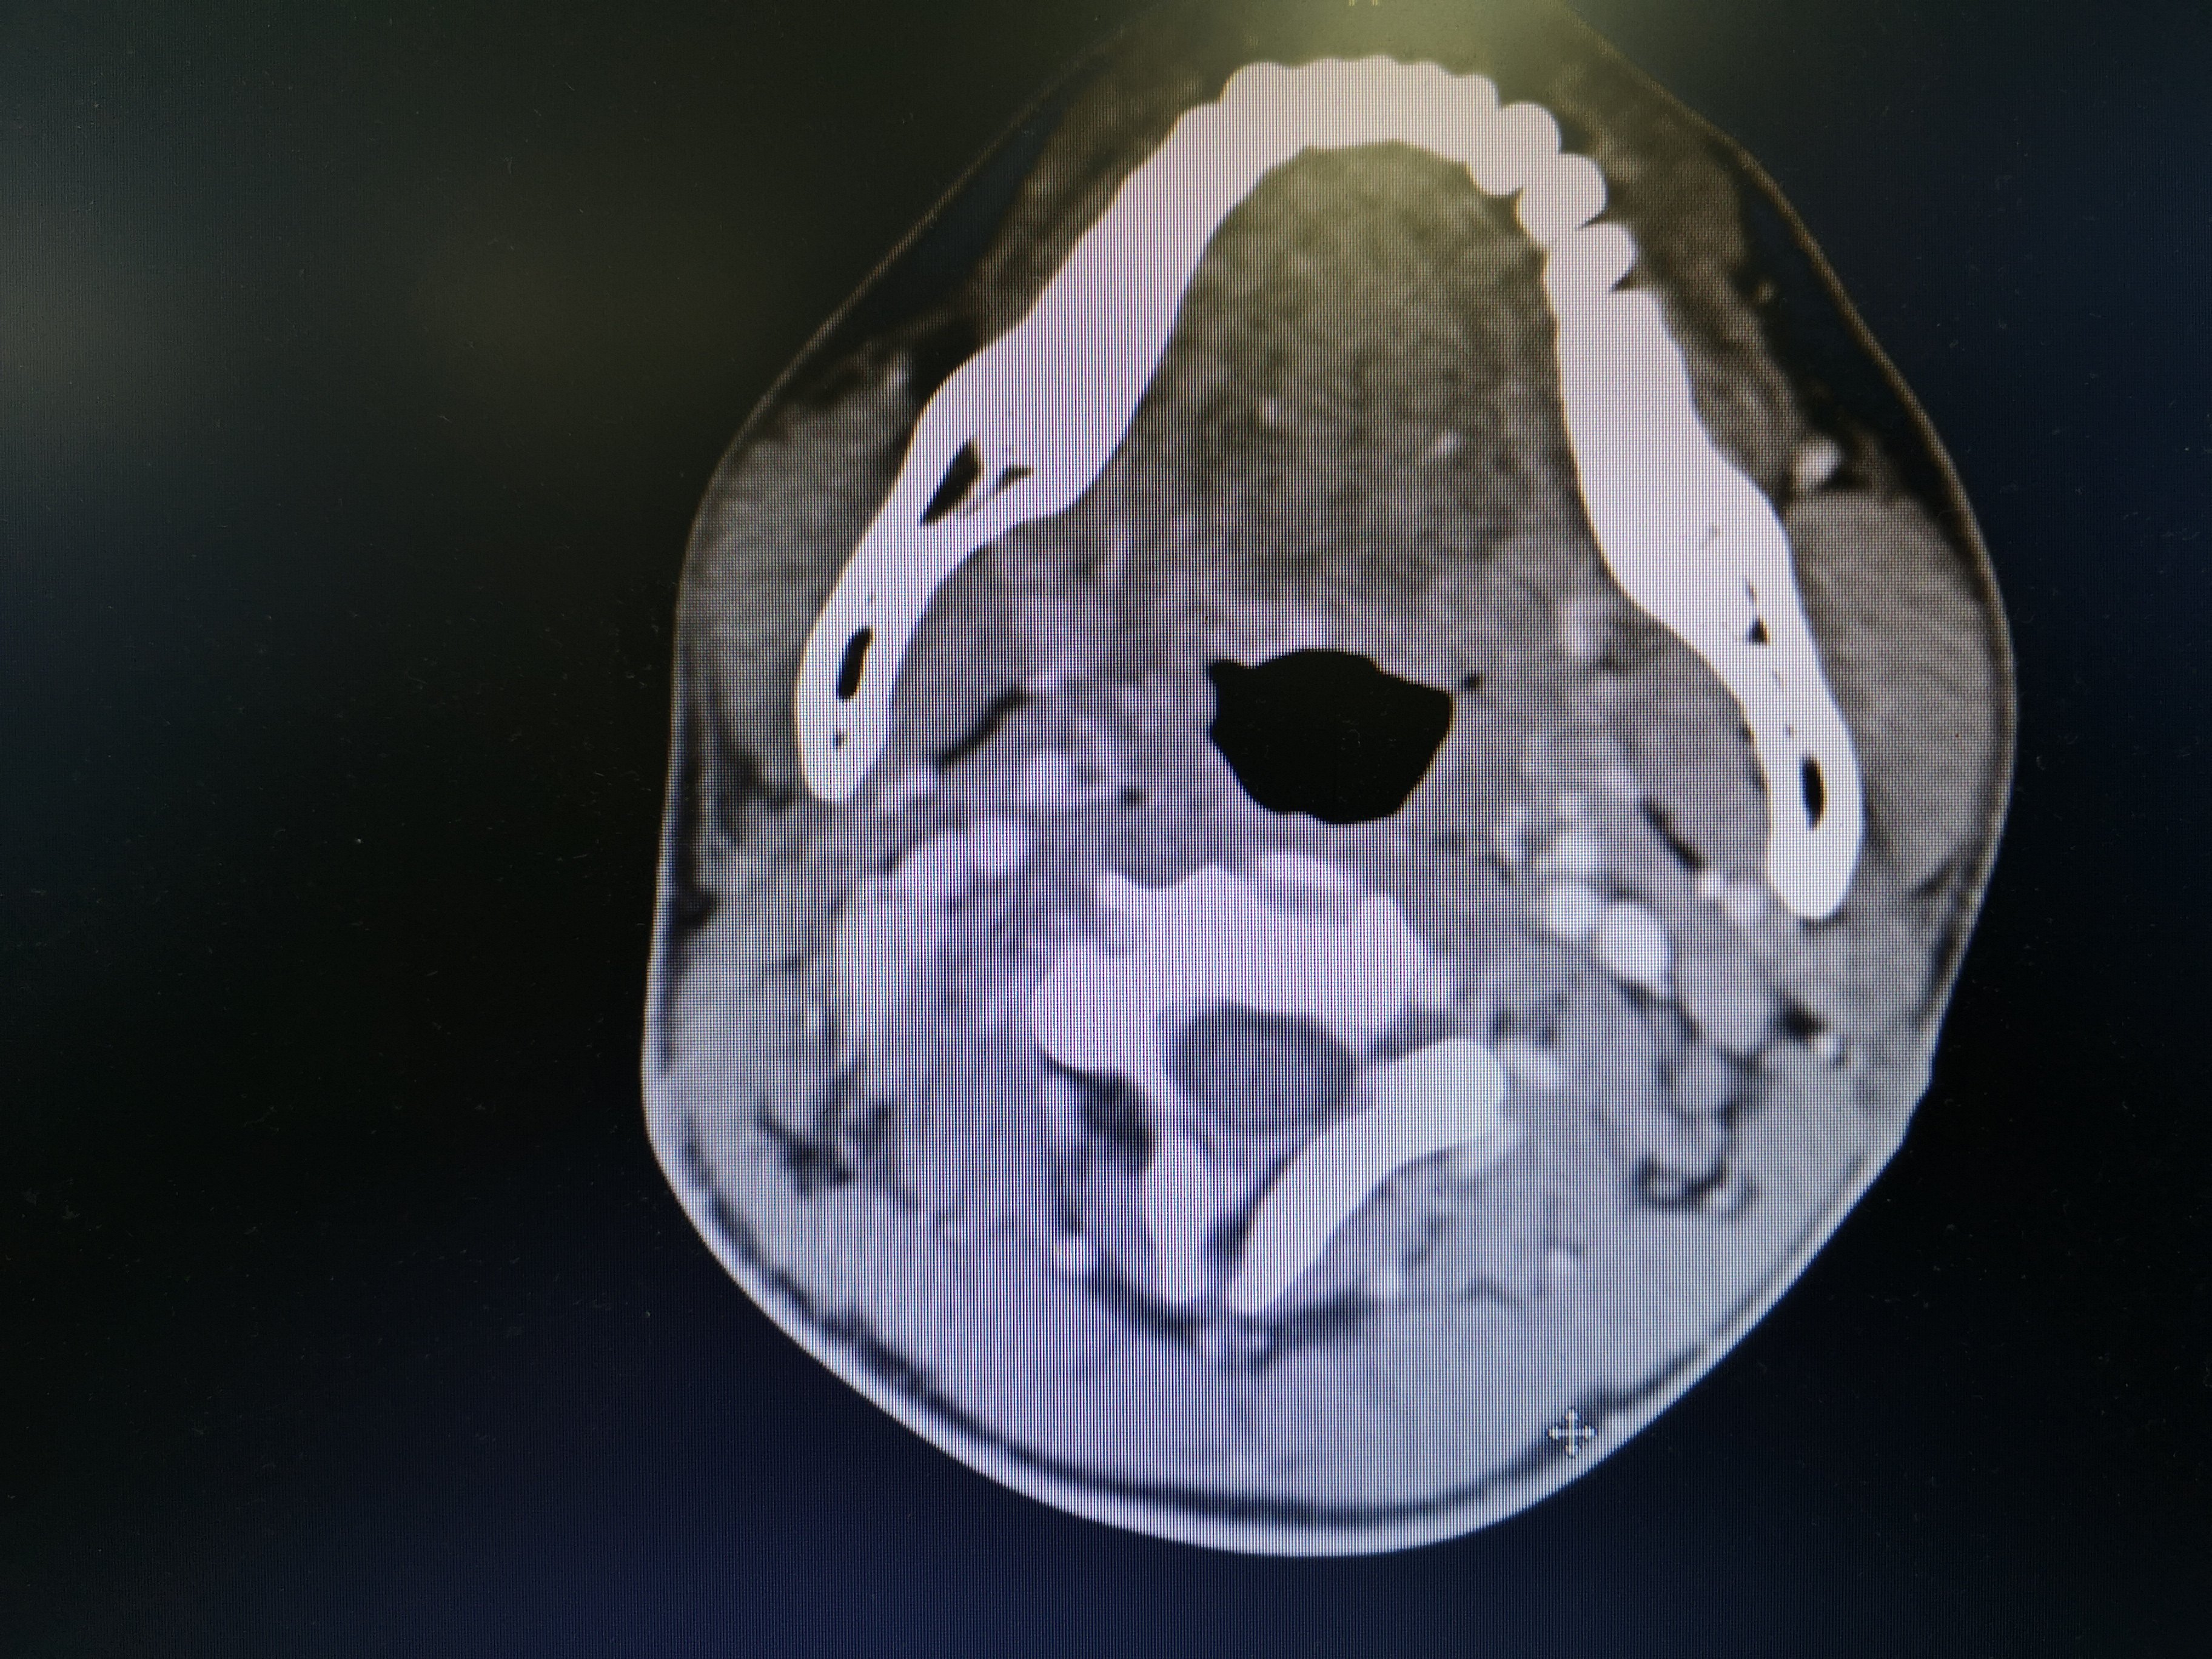

病例2 右2,右4R区,左6区残留,颈部切口清扫,未开胸